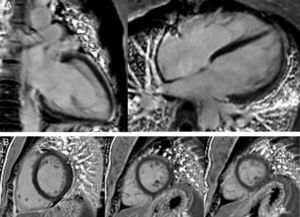

The CMRI revealed marked trabeculation in the apical segments of the LV with a diastolic ratio of noncompacted/compacted layers of 2.6, fulfilling CMRI criteria for noncompaction (Figures 2–4). LV mass was within normal limits and no delayed enhancement suggestive of fibrosis was detected after gadolinium administration.